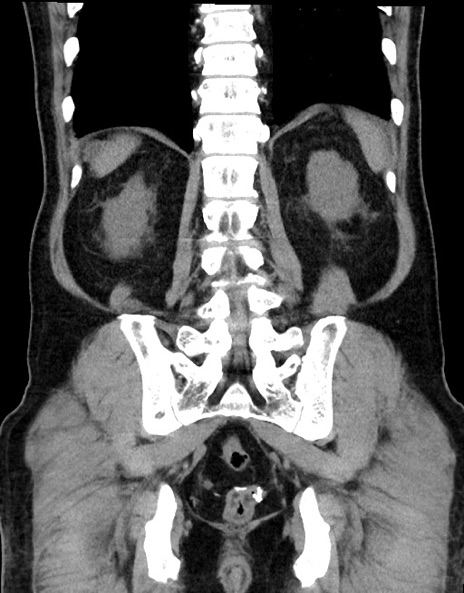

症例15(冠状断像)

【症例】70歳代男性

【主訴】腹痛

【現病歴】今朝から腹痛あり。全体的に痛い。特に左上の方。排ガスが今日はない。冷や汗が出る。

【既往歴】直腸癌術後

【身体所見】左側腹部〜上腹部に圧痛あり。腹膜刺激症状明らかなではない。軽度反跳痛。左下腹部に術後瘢痕あり。

【データ】WBC 7700、CRP 0.02